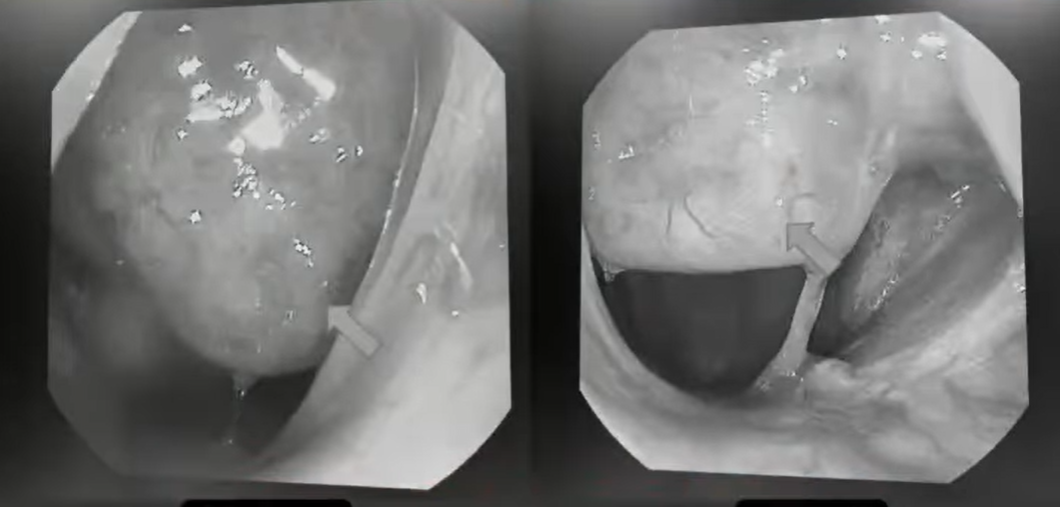

張弘透露,其用鼻腔內視鏡進行詳細檢查,形容「我在檢查左邊鼻子時,發現他鼻腔底端有一個滿大的腫瘤,腫瘤把整個空間幾乎都填滿,堵住後鼻孔,所以造成左邊鼻塞」。經切片檢查化驗確定為鼻咽癌,患者後續在醫院接受化療、放射治療。